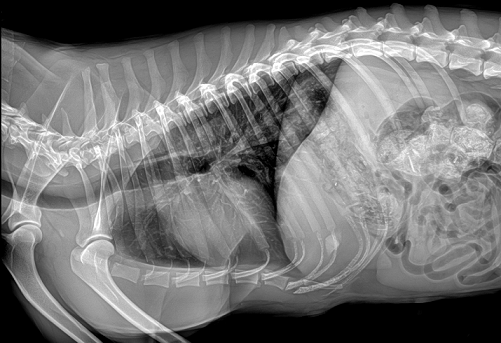

國(guó)產(chǎn)品牌普愛醫(yī)療寵物dr采用非晶硅平板探測(cè)器,可以令動(dòng)物影像成像清晰而快速,基本上5s左右就能使動(dòng)物影像清楚成像且無拖尾現(xiàn)象,而且分辨率高,極限空間分辨率可達(dá)到5.0Lp/mm;

普愛醫(yī)療寵物dr拍攝的高清照片

同時(shí),寵物影像成像尺寸較大,成像尺寸可達(dá)43cm x 43cm,并且以DICOM格式儲(chǔ)存數(shù)據(jù),極大的方便了醫(yī)療工作者們追蹤檢查時(shí)使用。同時(shí)還支持窗寬、窗位、放大、旋轉(zhuǎn)、正像和負(fù)像轉(zhuǎn)換等顯示功能。如果您想購(gòu)買普愛醫(yī)療寵物dr,或了解具體技術(shù)參數(shù),歡迎聯(lián)系我們。